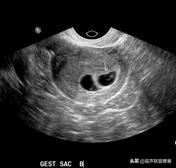

妊娠40天,见到卵黄囊、胚极及心管搏动, HCG12800U/L。

妊娠35天,高分辨的超声检查就可能见到心管搏动、胚极及卵黄囊。

卵黄囊高分辨超声图像,妊娠40天

一个孕囊有两个卵黄囊,单卵双胎。